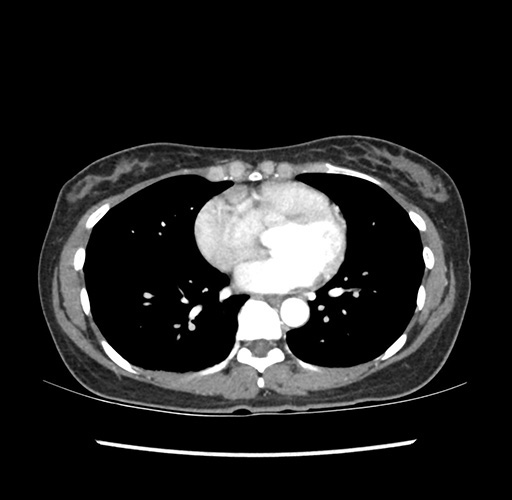

Imaging Analysis

Look through the patient's CT scan to identify any areas of concern for the necessary procedure.

Based on your CT findings, which issue(s) would give reason for "planned slowing down moment(s)" in this case?